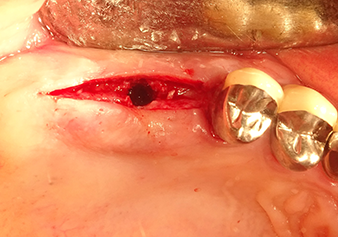

The I2A instrument (diameter 2.0 mm) was then used to perforate the sinus floor intermittently and on the smallest scale possible. This special piezosurgical method ensures that the Schneiderian membrane is not damaged. When the Z25P was used, the membrane was already lifted slightly by the coolant supplied via the instrument tip (Fig. 3). The coolant quantity was just 50% in order to avoid high pressure in the implant bed.